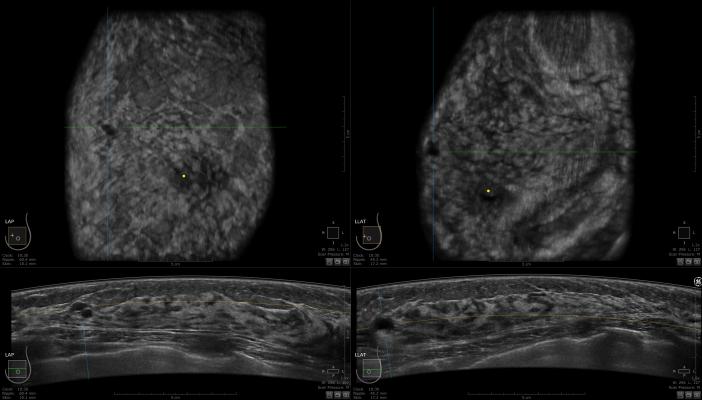

Patients in the study who opt to omit radiation as part of their treatment after lumpectomy will have follow-up examinations every three months for five years. The examinations will include breast imaging (mammograms or MRIs [magnetic resonance imaging]), and patients will be asked to fill out surveys on quality of life and the cosmetic aspects of their treatment. Their results will be compared with those of the controls: patients who opted to have the standard radiation.

Mitchell herself has another study in which she is looking at shortening the radiation treatment time for node-positive invasive breast cancer from a six- to seven-week course to a three- to four-week one. A co-investigator on Mitchell's HER2 study, Jamie Wagner, DO, chief of the breast surgery division (CK), is working on a national trial looking at de-escalating treatment for all types of breast cancer that are typically treated with chemotherapy followed by surgery. In that trial, the investigators are using extra imaging — MRIs and mammograms — to predict which tumors will be gone after chemotherapy. The next step would be to omit surgery for those patients.